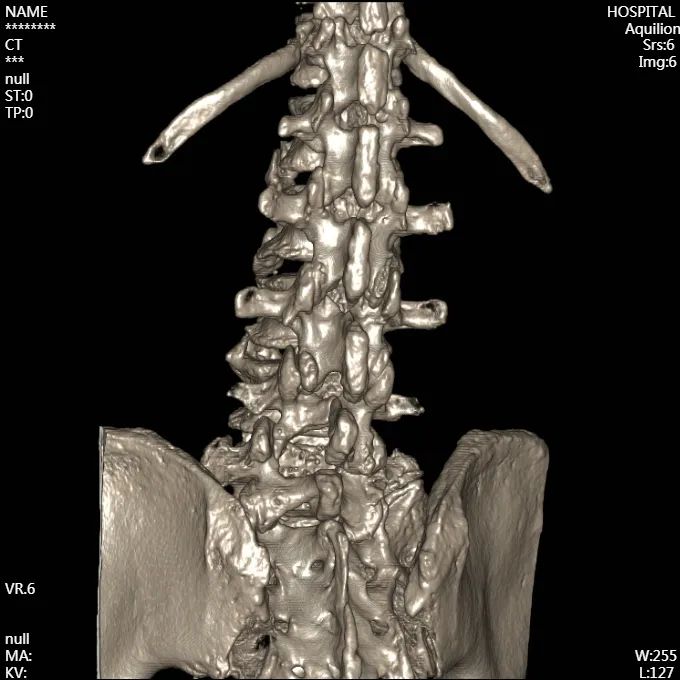

术后

腰椎CT成像

从影像上看出,患者术后神经压迫情况得到了改善